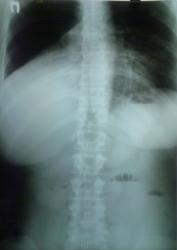

Женщина. Поступила в хирургическое отделение с диагнозом "кишечная непроходимость". Дежурный лаборант выполнила обзорный снимок брюшной полости уж больно "заковыристо". Что скажете?

Описывая это "произведение" на следующее утро назначаю контроль, в т.ч. и грудной клетки в правой боковой проекции

Беседую с пациенткой...да кишечные проблемы были, уже прошли...около 6-8 ми месяцев назад болеела (основная жалоба - кашель), лечилась, в т.ч. стационарно, обследовалась, в т.ч  КТ в ООД - сказали все нормально...живите мол и дальше. Данные предыдущих исследований обещают доставить с понедельника, будем и сами ее докручивать. Ваше мнение, коллеги?

Репродукции рентгенограмм нерезки, бронхов практически не видно..., думаю здесь ателектаз S7, S8.  возможно, с некоторым выпотом в главной междолевой щели.

Ателектаз средней доли (красный) + релаксация купола диафрагмы справа (зеленый) дали такое гомогенное интенсивное затенение. Валентин Львович, Вас не глючит. Больная, видимо, поела.

Верхней доли то справа нет....

Значит Рак верхнедолевого бронха?

У меня пока, как рабочая версия, аденома среднедолевого бронха.

Поддерживаю Medea, объёмное уменьшение средней доли присутствует! За счёт чего (пневмофиброз/онко?) предстоит узнать на дообследовании.